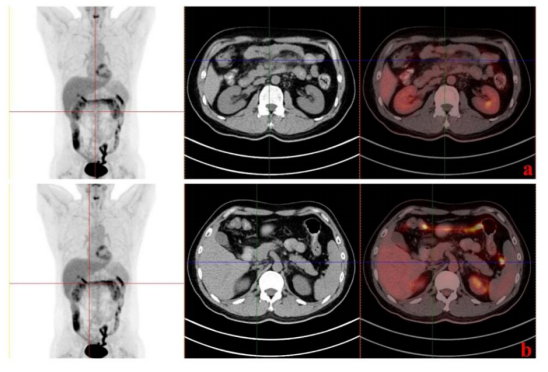

一名40岁男性患者于2021年5月上旬无明显诱因,剑突下腹部可触及肿块,坚韧无痛,无恶心、呕吐、体重减轻等不适。经过CT、肿瘤穿刺、免疫组化等多项检查(图2),患者被确诊为淋巴瘤,淋巴造口系统肿瘤以滤泡性结构为主,考虑滤泡性B细胞淋巴瘤,2级,3期,FLIPI评分2分。而后患者经过多轮化疗,病情稍好转。2023年9月5日时,患者复查PET-CT(图2B-b)提示肿瘤处于抑制状态,治疗后部分缓解(PR),但仍然残留部分病灶,主治医师决定对患者进行CAR-T治疗。

图2. CAR-T输注前的PET-CT图像及病理切片。(A) CAR-T输注前腹部肿块病理结果。a:苏木精伊红染色。b-e: Bcl-2阳性,Bcl-6阳性,CD21阳性,CD20阳性。(B)腹部初始诊断及有效治疗的PET-CT影像时间。a:2021-5-26。b: 2021-12-14。(C)腹部复发PET-CT时间及免疫维持治疗。a:2023-2-16。b: 2023-9-5。

此外,我们检测CD4+/CD8+T细胞的比例发现其在第60天下降后增加,而CAR拷贝数先增加后减少。我们推测,肿瘤可能在第60天左右复发,休眠的CAR-T细胞被激活,导致CAR拷贝数升高,细胞毒性CD8+ T细胞增殖并杀死肿瘤,第四个月PET-CT(图5)提示患者已完全缓解(CR)。